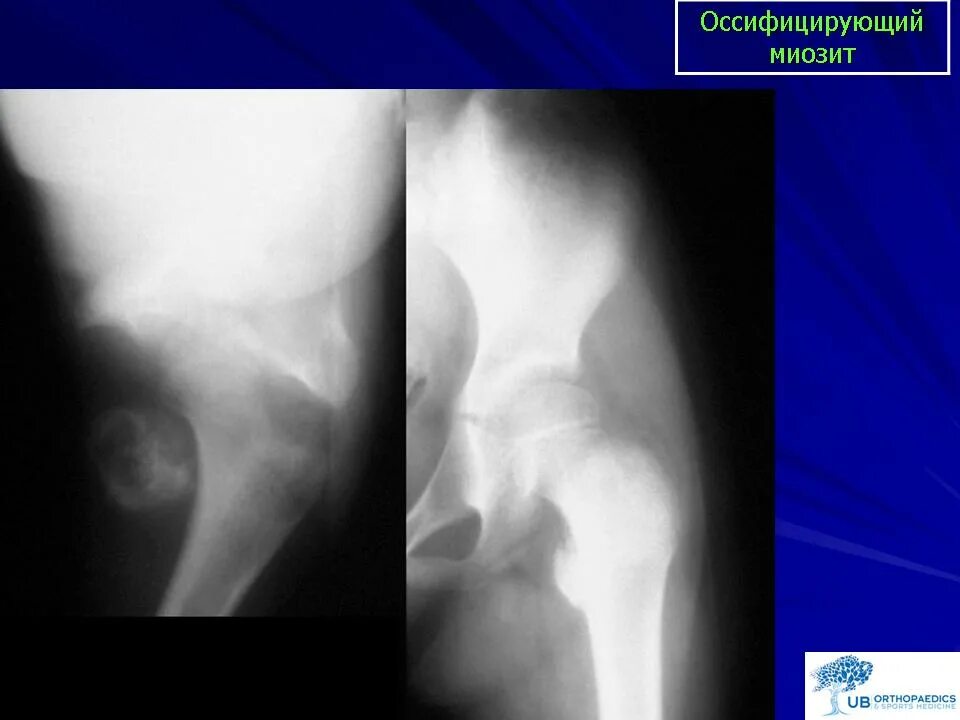

Оссифицированный миозит